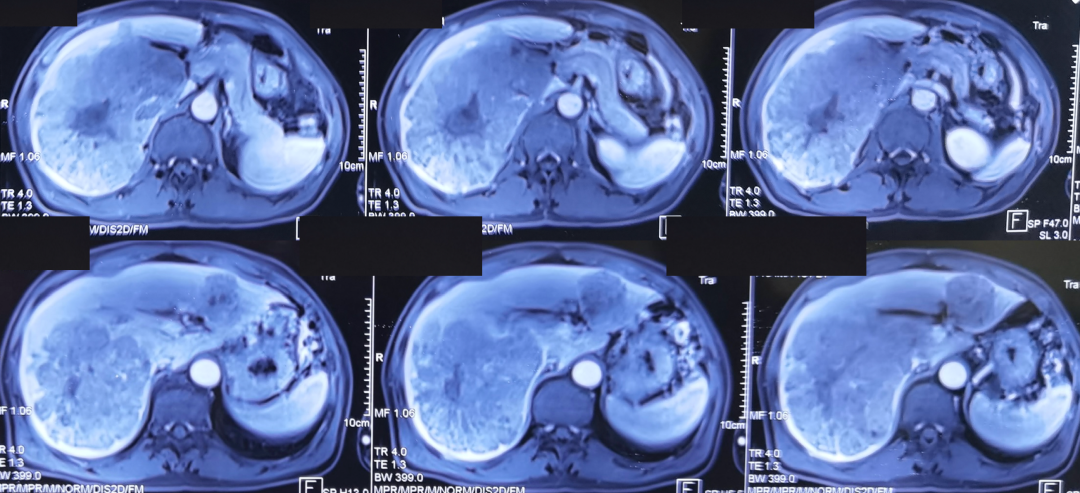

患者男性,57岁,既往慢乙肝病史。1年半前发现肝占位就诊。就诊时化验肝功能Child A5,AFP>40 000 ng/ml。腹部增强核磁提示:肝内多发肝癌,最大者直径约25 cm,占据右后叶、右尾状叶及部分右前叶,右肝及左外叶多发子灶(影像如图1所示)。

图1.首诊核磁影像